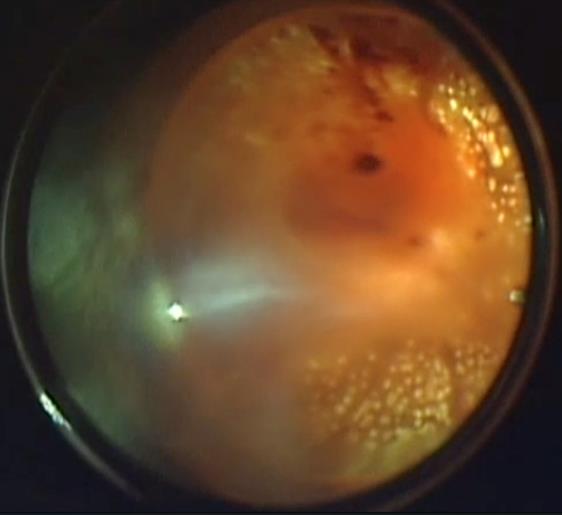

Die Glaskörperblutung vermindert die Transparenz der optischen Medien und bedingt eine deutliche Sehverschlechterung. Außerdem haben die Blutzellen eine toxische Wirkung auf die Netzhaut. Eine weitere Komplikation der Glaskörperblutung ist die Bildung pathologischer Membranen auf der Netzhautoberfläche (epiretinale Gliose). Diese Membranen, sofern sie nicht entfernt werden, können eine Netzhautablösung mit einer starken Verschlechterung der Sehkraft verursachen. Eine frühzeitige chirurgische Entfernung der Glaskörperblutung und der epiretinalen Gliose verbessert die Prognose für die Sehkraft deutlich.

Chirurgische Behandlung bei Glaskörperblutung und epiretinaler Gliose

Die operative Therapie der Glaskörperblutung und der epiretinalen Gliose wird mittels Pars Plana Vitrektomie durchgeführt, der modernen Methode zur Behandlung von Glaskörper- und Netzhauterkrankungen. Diese Operation kann sowohl in Allgemein- als auch in Lokalanästhesie durchgeführt werden. Während der Operation werden Blutung und Membranen mit Hilfe eines speziellen Operationssystems durch minimale Öffnungen an der Augenwand entfernt.

Unabhängig von möglichen postoperativen Komplikationen bildet die Pars Plana Vitrektomie die einzige wirksame Methode zur Therapie verschiedener Formen der diabetischen Retinopathie.

Entfernung der Glaskörperblutung:

vor der Operation

nach der Entfernung mittels Vitrektomie